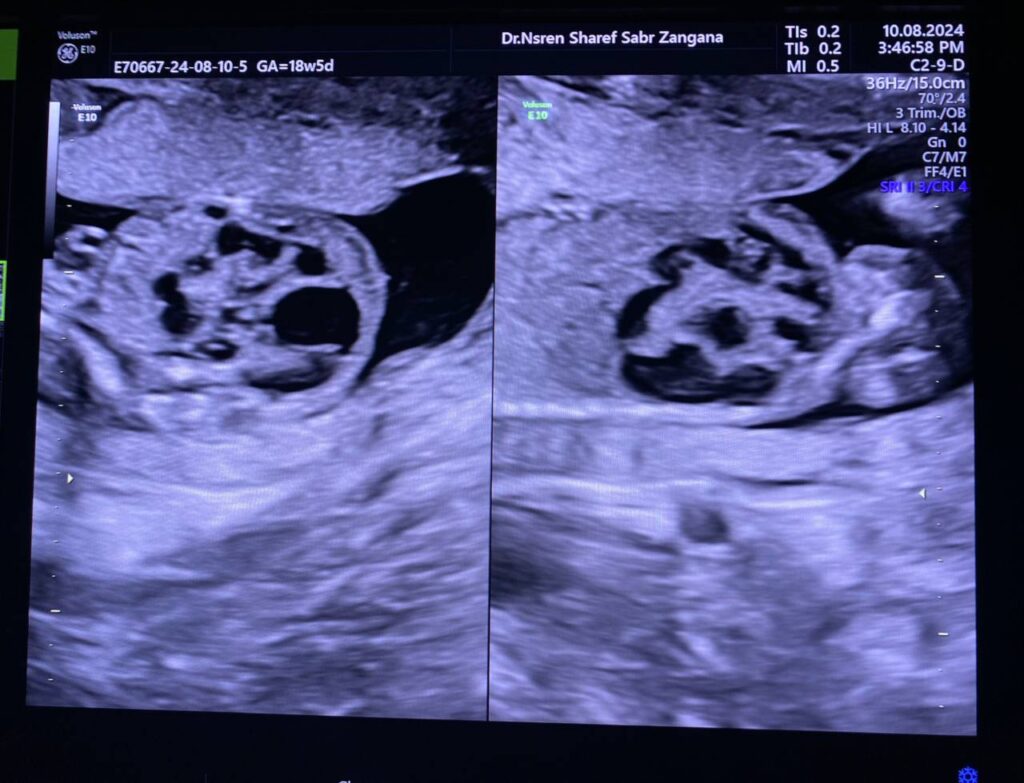

Same fetus when become about 19weeks

Right kidney enlarge in size 34x21x29mm, occupy by numerous

cysts of variable sizes, the largest 13mm , normal left kidney , polycystic ?